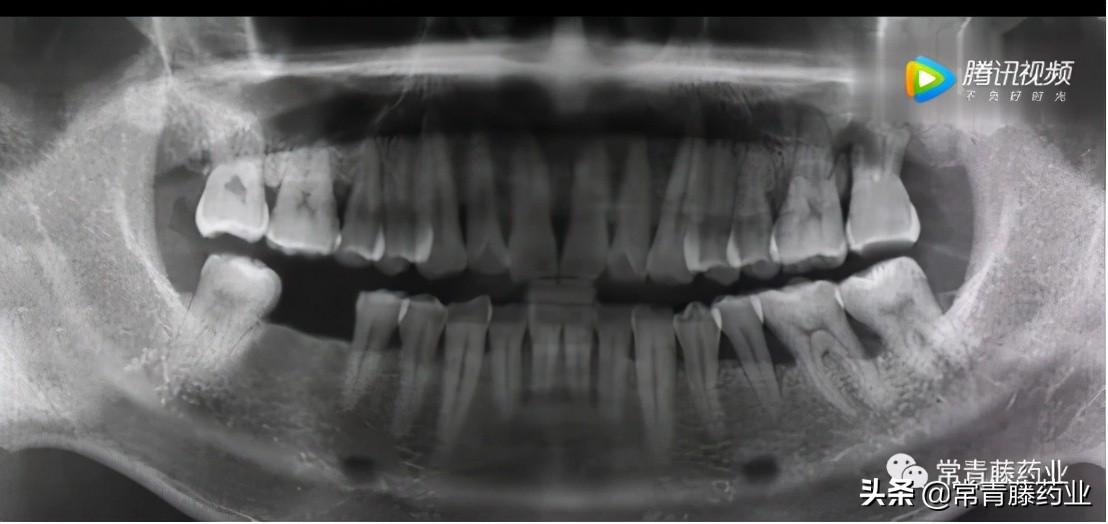

今天給大家科普一下種牙的知識!在種牙開始之前需要進(jìn)行口腔檢查和全景片、頜骨CT拍攝以確定牙周是否有炎癥、牙槽骨頭是否擁擠以及牙體情況等。(如下圖)